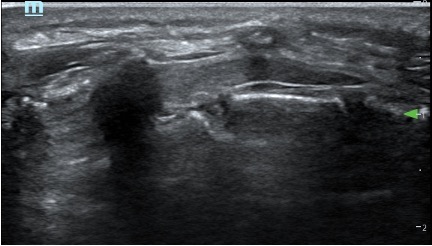

- At birth, the ossification centres of the spine are at an early stage of development; it is therefore possible to obtain excellent spinal images in neonates. With age and increasing ossification, the US window to the spine diminishes (the ossification is complete at 21 years old)

Caudal in a two year old